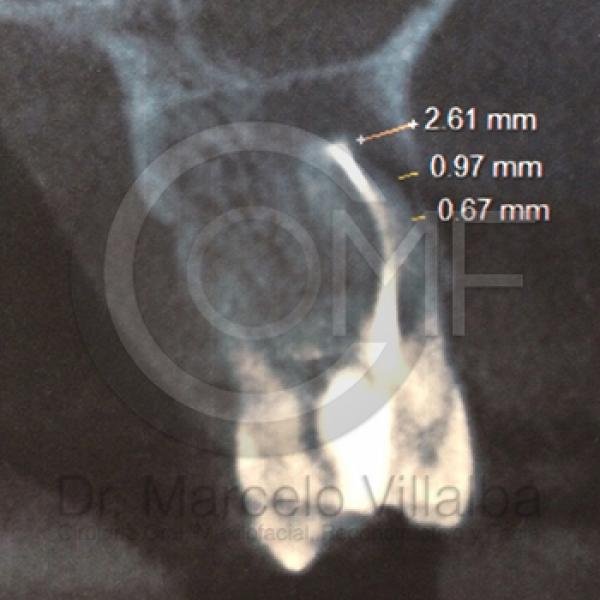

Contenido Sensible y Gráfico

Si usted no pertenece al área de la salud, las imágenes pueden ser muy explícitas.